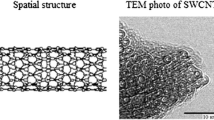

In the last era, nanoparticles (NPs) were studied as promising drug delivery systems for the transport of drugs to the tumor site due to their advantages in cancer treatment: reduced size, controllable structure, and tumor-targeted drug release (Shokooh et al. 2022). An emerging approach based on nanotechnology is the use of carbon nanotubes (CNTs) as a therapeutic route for TNBC. CNTs are cylindrical structures consisting of graphene, with lengths up to microns and a diameter of range in nanometers, which are classified into single- and multi-walled CNTs (SWCNTs and MWCNTs), depending on the number of layers of which they are made up. Moreover, CNTs are highly hydrophobic and require functionalization to improve their solubility in aqueous solutions before their use in biomedical applications (Rathinavel et al. 2021). The addition of functional groups on CNTs' surface improves water solubility and facilitates the complexation of other molecules or drugs with CNTs (Dubey et al. 2021). As nanocarriers, CNTs present important advantages over conventional therapeutic agents, such as targeted and controlled delivery at the tumor site, minimization of side effects, enhanced internalization and efficacy of antineoplastic agents, and delivery of combination of two or more drugs, which highlight their potential use as tools in cancer therapy (Grobmyer et al. 2011; Mendes et al. 2015).

Synthesis and characterization of SWCNT–COOH–CDDP complexes

Carboxyl-functionalized single-walled carbon nanotubes (SWCNT–COOH) were obtained by covalent functionalization of SWCNT through chemical oxidation. Further, SWCNT–COOH was functionalized with CDDP to obtain carboxyl-functionalized single-walled carbon nanotubes conjugated with CDDP (SWCNT–COOH–CDDP). The detailed procedure of synthesis and characterization of the complex is presented in a previous study (Badea et al. 2022).